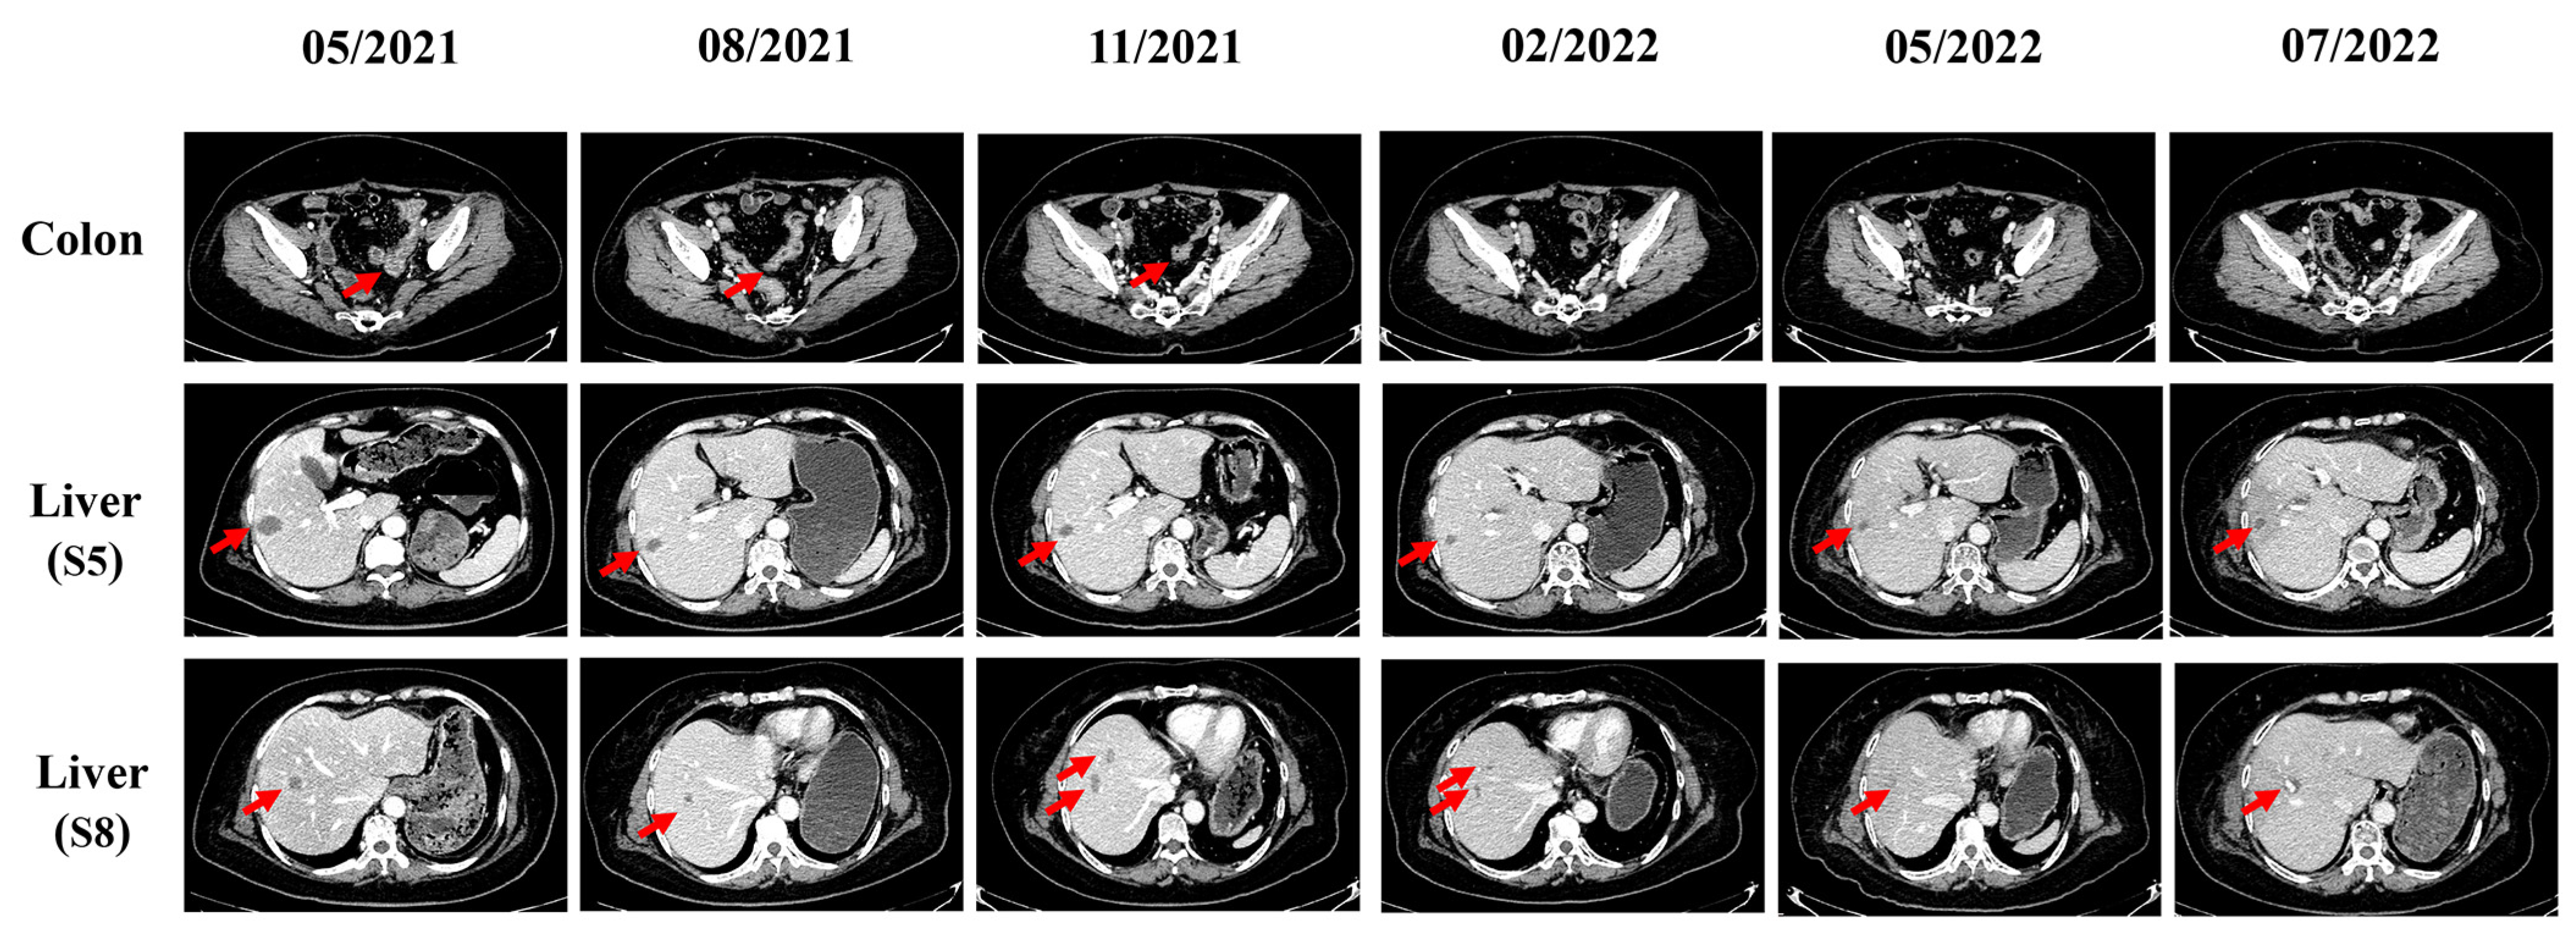

2. Case Description